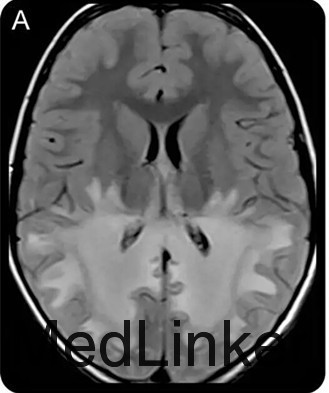

查体发现患儿皮肤色素沉着及低血压。神经系统查体提示理解困难,双眼视力下降、共轭凝视不良,辩距不良,步态不稳。脑脊液蛋白升高。头颅MRI如下图。清晨皮质醇水平降低,促肾上腺皮质激素兴奋试验证实肾上腺功能不全功能。神经遗传学检测提示ABCD1基因突变

ALD是一种先天性代谢性疾病,也是最常见的溶酶体病之一。属于X-连锁遗传病。本病特征性的影像学改变是MRI可见双侧顶枕区白质对称性分布的蝴蝶样长T1长T2信号,早期即可以胼胝体压部受累,并将两侧病灶连为一体。(神经病学俱乐部)本病一般预后较差,在出现神经症状后1~3年死亡。